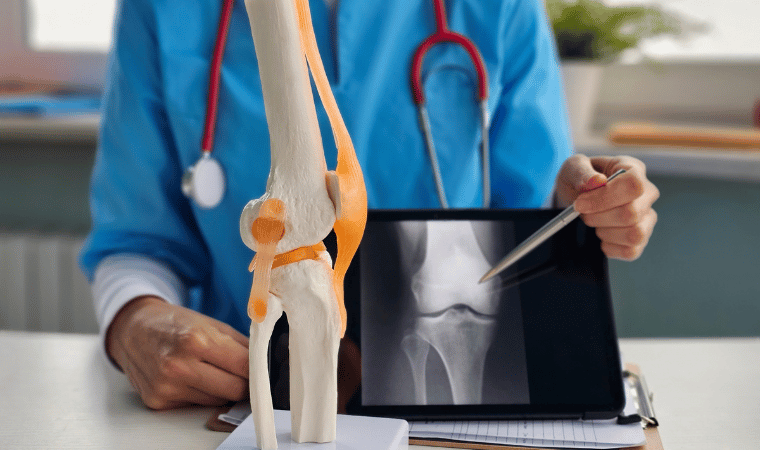

Trauma surgery is a surgical specialty that utilizes both operative and non-operative management to treat traumatic injuries, typically in an acute setting.Trauma surgeons generally complete residency training in General Surgery[ and often fellowship training in trauma or surgical critical care. The trauma surgeon is responsible for initially resuscitating and stabilizing and later evaluating and managing the patient. The attending trauma surgeon also leads the trauma team, which typically includes nurses and support staff as well as resident physicians in teaching hospitals.

Trauma is the injuries suffered when a person experiences a blunt force. You may also hear trauma referred to as a “major trauma.” Many trauma patients are the victims of car crashes, stabbings, and gun shot wounds. Trauma can also be caused by falls, crush type injuries, and pedestrians being struck by a car. Traumatic injuries can affect internal organs, bones, the brain, and the other soft tissues of the body. No area of the body is immune to trauma, but trauma can range from minor (hitting your finger with a hammer) to major (being hit by a car traveling at a high rate of speed or falling off of a building).